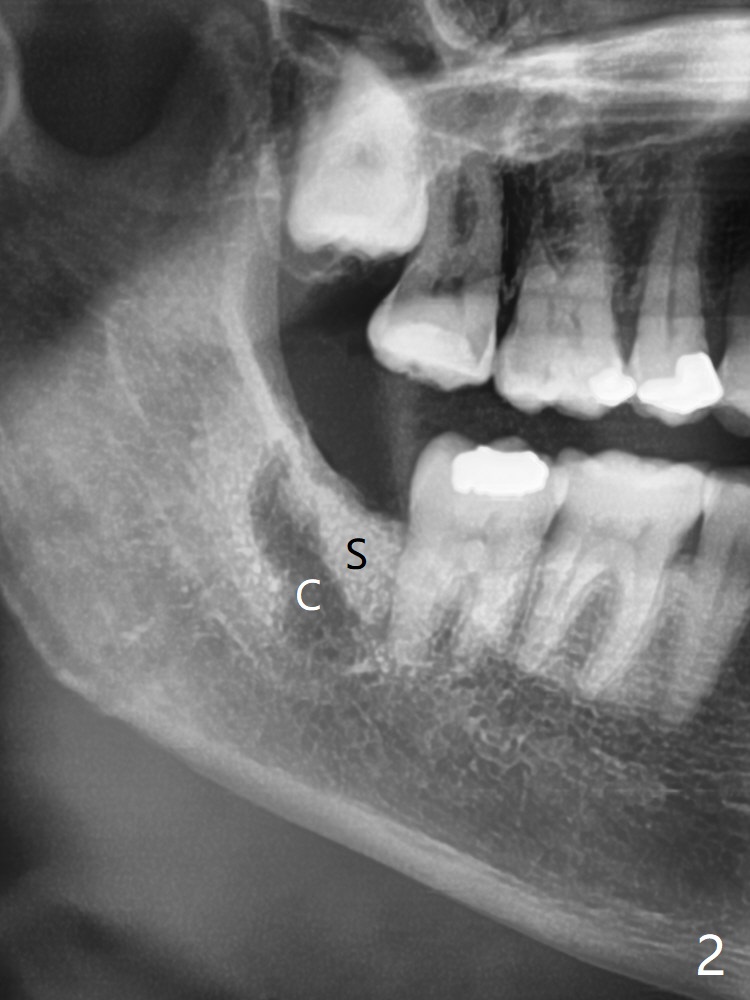

56岁女因右下智齿牙龈出血要求拔除,切开后发现智齿周围骨质吸收,有许多肉芽组织(图一:*),拔除容易,清创时远中牙龈出血,需要压迫止血,之后在牙槽窝远中,近中放置胶原塞(图二:C)和粘性骨粉(S),上面覆盖PRF,使用4-0 PGA缝线,近中伤口缝合不紧。术后两个月随访时拍摄全景片证实骨粉没有明显流失(病人抱怨术后骨粉流失,逐渐减少),第二磨牙远中没有骨板,第三磨牙近中牙槽嵴接近正常外形(图三:箭头)。Return to Plug Allograft 儿子 Xin Wei, DDS, PhD, MS 1st edition 06/07/2021, last revision 08/01/2021